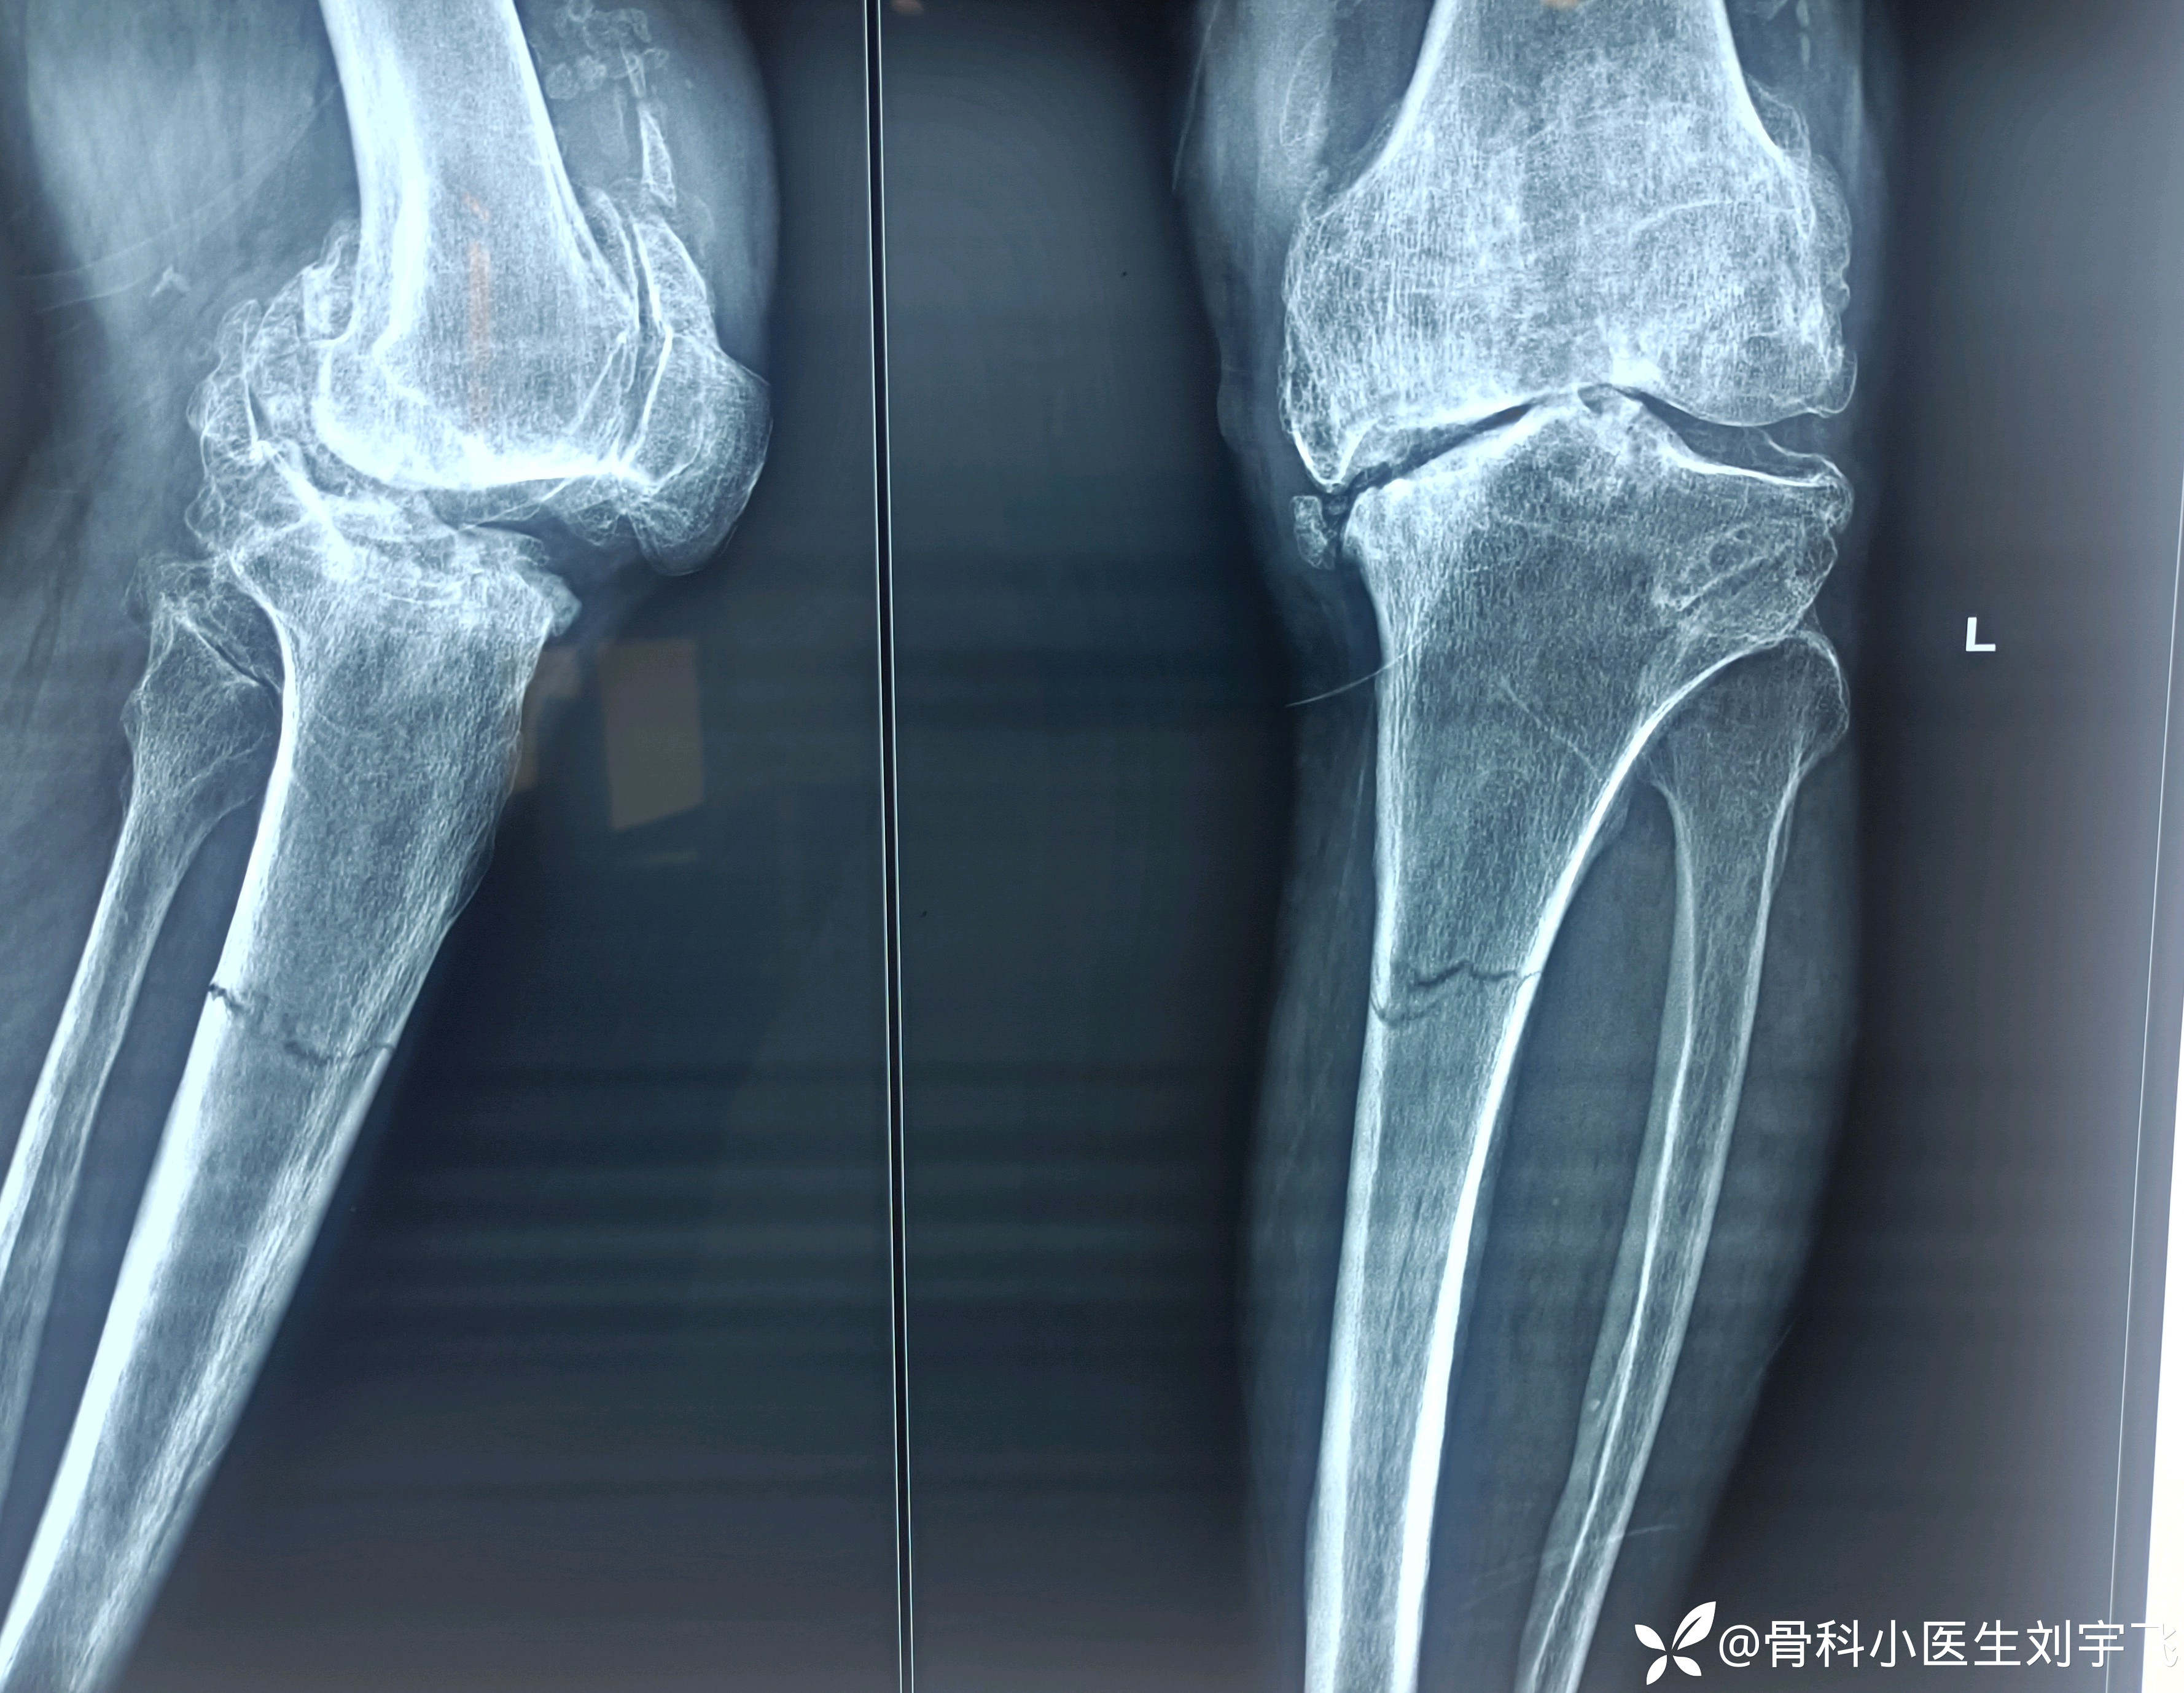

患者主诉无诱因膝关节疼痛胫骨中上段骨折?

患者老同志75岁无诱因疼痛半个月左右, 刚从门诊进来双膝关节明显变形,扶着拐说以前来过医院买过膏药用过药就好了,今天过来也想买点外用药,(这时候如果不仔细查体就会以为是骨性关节炎)然后查体发现小腿按压痛明显 但是看外观又没有明显红肿和外伤,所以我说老同志照个片子看看膝关节里面是怎么回事是什么原因疼痛,这时候老同志一直强调以前来过配一点药就要走,这时候我也有点动摇了 单纯的骨性关节炎关节畸形 变形很重可能就是炎症反应,我又再次劝说老同志说看看以后在配药放心,然后做了一个膝关节包小腿的x线,胫骨中上段骨折,片子出来后 庆幸没有让老同志直接开药走,所以好多病人来了都应该自己上手摸一摸看一看差查体,对病人负责也对自己负责,总结就是这个同志刚进来给我提供的消息让我的临床思维一下到了骨性关节炎这里